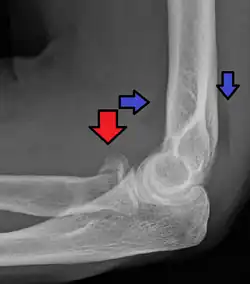

CT scan showing a radial head fracture -

Radial head fracture seen on 3D CT reconstruction